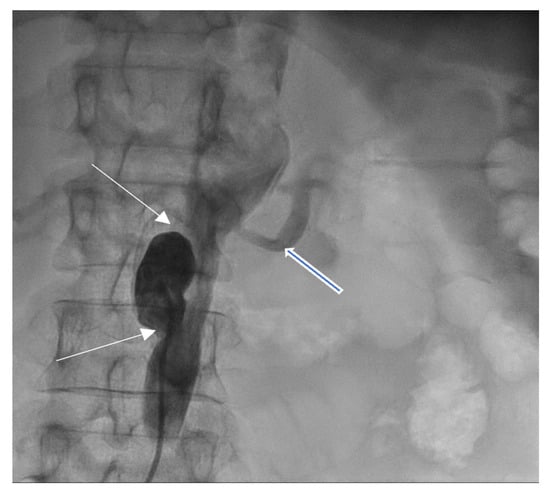

2. Case Presentation